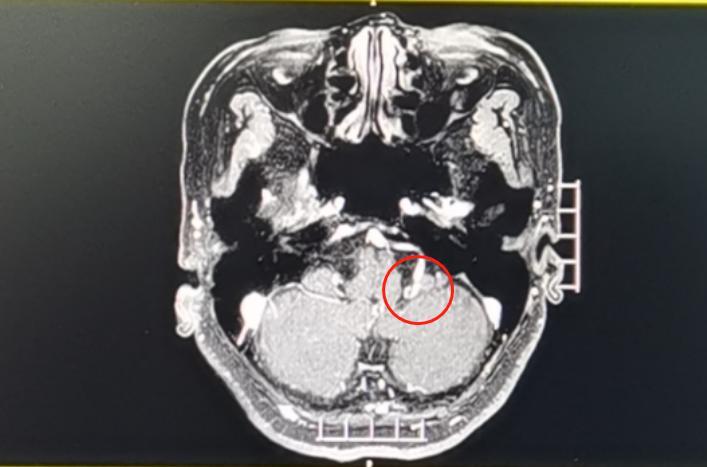

但半脸频繁抽搐的原因是脑肿瘤吗?根据面诊观察及结合病史,完善相关检查,也未见陈姨有颅内肿瘤等占位性病变,该院副院长鲁明最终诊断陈姨为面肌痉挛。

据介绍,面肌痉挛是面神经周围的血管对神经根压迫,造成面神经脱髓鞘改变,引起神经异常放电而出现神经传导功能的异常,即发生了“神经短路”。

“可以通过微创手术,在神经与血管间垫入米粒大的垫片,解除血管压迫,使面肌痉挛症状得到缓解。”鲁明介绍。

4月17日,鲁明团队在显微镜下为患者实施了左侧面神经微血管减压手术。日前陈姨顺利出院。